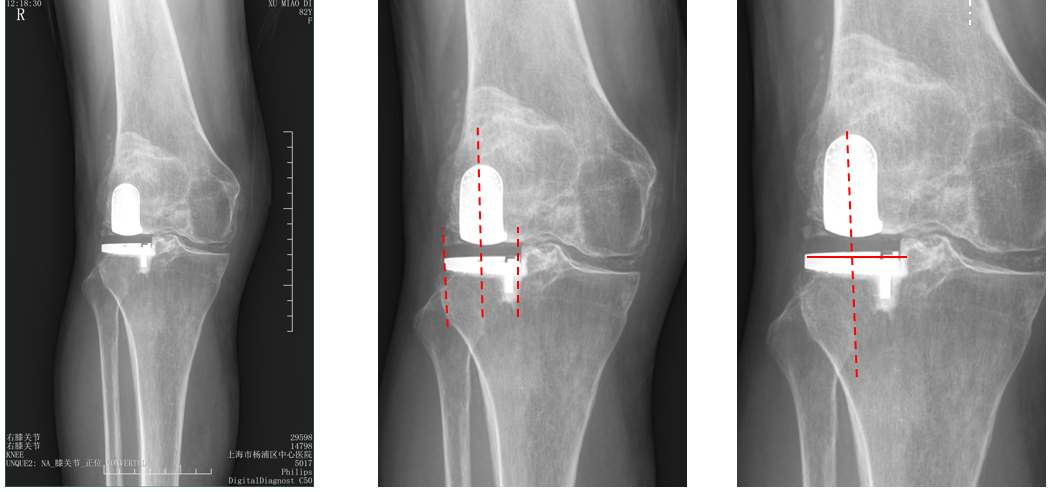

股骨假体偏内放置

AP位胫骨与股骨假体位置:股骨假体中轴线与胫骨假体中线不一致,偏内侧,且外翻。

股骨假体偏外放置

AP位胫骨与股骨假体位置:股骨假体中轴线与胫骨假体中线不一致,偏外侧,且内翻

胫骨假体后倾角度大

侧位片胫骨假体位置:胫骨假体后倾15°,前后缘齐平。

股骨假体偏小

侧位片股骨假体位置:股骨假体偏小,与胫骨假体后缘不齐平;屈曲35°,未包容股骨后髁。